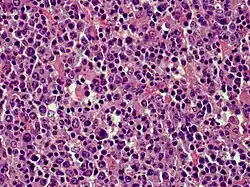

Cutaneous diffuse large B-cell lymphoma (DLBCL)

Cutaneous B-cell lymphomas (CBCL), more recently termed Primary cutaneous B-cell lymphomas and lymphoproliferative disorders (PCBCLPD), are a group of disorders that typically present as skin lesions consisting of proliferating B-cells. B-cells are a type of lymphocyte involved in regulating immune responses. (The "primary" used to designate cutaneous lymphomas indicates that the lymphoma was first diagnosed as limited to the skin and there was no evidence of spread to extracutaneous tissues for 6 months after the diagnosis was first made.[1]) Since its original definition in 1997, CBCL has been considered to have a varying number of subtypes by the European Organisation for Research and Treatment of Cancer, i.e., EORTC, and World Health Organization, i.e., WHO.[2] The latest revised classification of CBCL, which was published by EORTC in 2022, lists the following three main subtypes of CBCL (now termed PCBCLPD):[3]

Because recent studies had shown that primary cutaneous marginal zone lymphoma, which was formerly classified as a subtype of the MALT lymphomas: a) has a distinct microscopic histology and gene expression profile; b) spreads to extracutaneous tissue in only 4 to 8.5% of cases; c) has a 5 year disease-specific survival in excess of 99% even in patients not receiving aggressive therapy; and d) has pathological findings that overlap the benign cutaneous disorders termed cutaneous lymphoid hyperplasia. Consequently, EORTC, 2022, renamed primary cutaneous marginal zone lymphoma as primary cutaneous marginal zone lymphoproliferative disorder.[3] Primary cutaneous follicle center lymphoma is also an indolent lymphoma.[4] The majority of patients achieve complete remissions following surgery and/or radiation therapy. Its spread to extracutaneous tissues is rare (10%) and has a 5-year overall survival and disease-specific survival of 87% and 95%, respectively.[3] Primary cutaneous diffuse large B-cell lymphoma, leg type is an aggressive B-cell lymphoma that is often resistant to therapy and carries a poor prognosis,[5] i.e., they have a 5-year disease-specific survival rate of 43% or 70% depending on whether their cancer cells have or do not have, respectively, inactivating mutations in both of their CDKN2A genes.[6]